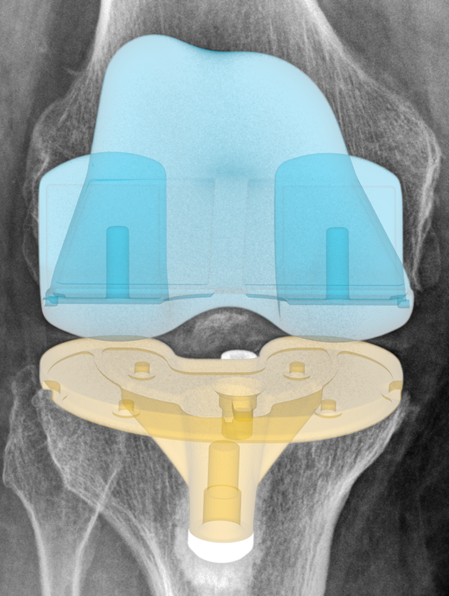

Intelligente Analyse der Positionierung und Leistung von Knieimplantaten

RAYLYTIC Image Lab ermöglicht hochpräzise Analysen der Implantatpositionierung und -leistung im Knie. Dazu gehören die Auswertung von Komponentenausrichtung und -rotation sowie die Messung von Implantatmigration und -abrieb, damit Sie schneller zu konsistenten und belastbaren Forschungsergebnissen gelangen.

Knie

- Hüft-Knie-Knöchel-Ausrichtungswinkel (HKA)

- Implantatkomponenten-Positionierung (6 Freiheitsgrade)

- Komponentenausrichtung (koronal & sagittal)

- Beinachse

- Femur-Tibia-Winkel

- Gelenklinien-Konversionswinkel

- Distaler Tibia-Winkel

- Proximaler Femur-Winkel

- Polyethylen-Verschleißquantifizierung

- Implantatmigration/-subsidence

Knie & Bein

Präzise Messungen der Knie und Beinanatomie sowie der Implantatpositionierung und Implantatleistung in der Knieendoprothetik.

● Implantatleisung und Implantatpostionierung

Beurteilung der Positionierung von Implantatkomponenten anhand von Standardröntgenaufnahmen

Polyethylen (PE) Einlagenhöhe & Abriebverhalten (Implant Wear)

Migration der Tibiakomponente